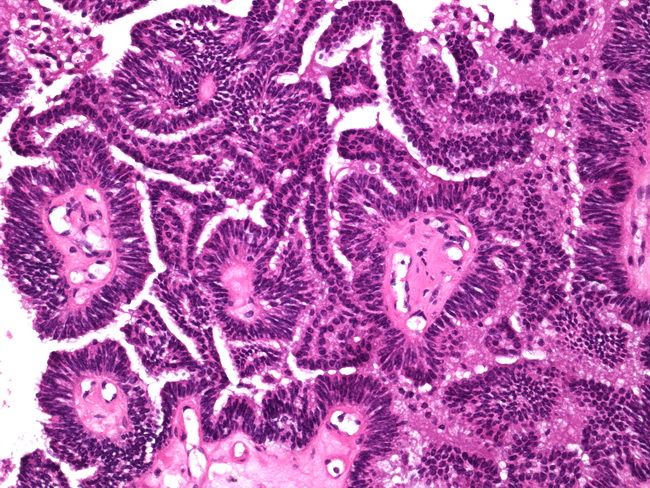

Папиллярный Рак Фото

Папиллярный Рак Фото 104 фотографий